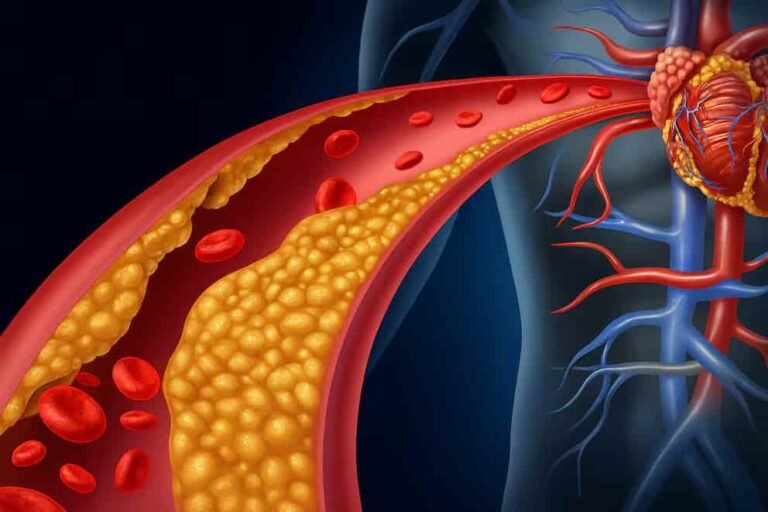

CrónicasCarga persistenteDiabetes, hipertensión, cáncer y enfermedad cardiovascular concentran alta demanda.